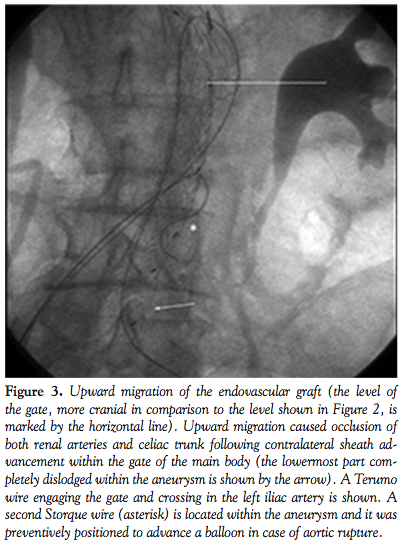

During this maneuver, the dilator of the sheath touched the entrance zone of the gate and dislodged the EVG moving it proximally in the thoraco-abdominal aortic segment causing complete occlusion of both renal arteries and celiac trunk (Figure 3). Despite careful sheath advancement under fluoroscopy guidance, the migration was so rapid that it could not be prevented by sheath retraction. A Radifocus wire was then advanced in the EVG body and by the means of a Simmons 1 catheter (Cordis) the contralateral leg was engaged in a cross-over fashion. A goose-neck 35 mm catheter (Cook) was then advanced from the left femoral artery enabling the capture of the Radifocus wire, whose tip was then

externalized. An over-the-wire 8.0 x 40 mm balloon (Wanda, Boston Scientific) was then inflated at 6 atm in the left common iliac artery to minimize iliac artery injury during manipulations. Then, two torque devices were tightly closed to trap the externalized left and right segments of the Radifocus wire. Under fluoroscopic guidance the devices were then used to forcefully push and tug downwards until the wire was placed in cross-over from the body to the contralateral gate, enabling downward displacement of the EVG and resumption of normal flow in both renal arteries and celiac trunk (Figure 4).